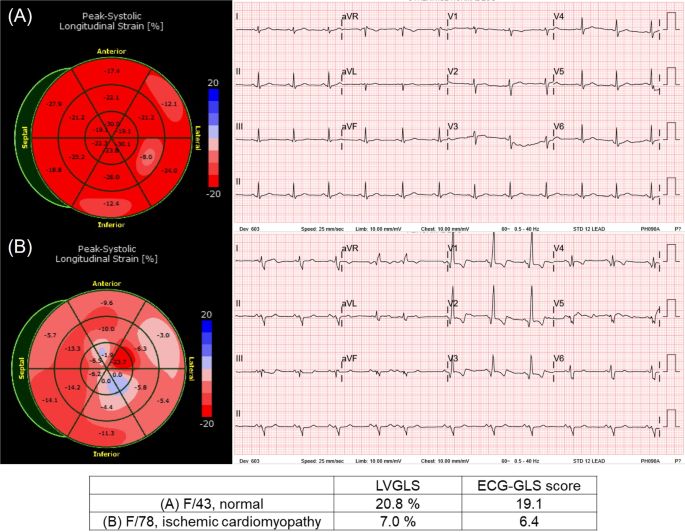

Echocardiographic images were obtained using comprehensive echocardiography in accordance with the guidelines of the American Society of Echocardiography12. LVEF was measured from apical four- and two-chamber views using the Modified Simpson’s method. LVGLS was measured using a built-in software in each echocardiography machine. For the training cohorts 2 and 3, the Image-Arena system (TomTec Imaging Systems, Munich, Germany) was utilized to measure LVGLS. For strain analysis, the endocardial borders were traced on the end-systolic frame defined by the QRS complex. The software tracked speckles along the endocardial border and myocardium throughout the cardiac cycle. The peak longitudinal strain was automatically computed by averaging regional strain values. The LVGLS was obtained from apical three-, four-, and two-chamber views. Because the LVGLS values are expressed as absolute values to avoid confusion, higher values represent better function. For patients with sinus rhythm, analyses were performed on a single cardiac cycle. For patients with atrial fibrillation, strain values were calculated as the average of three cardiac cycles. Representative cases are described in Fig. 2.

Representative case of LVGLS and ECG-GLS score pair. (A) A 43-year-old female who underwent echocardiography for routine checkup. (B) A 78-year-old female with ischemic cardiomyopathy.